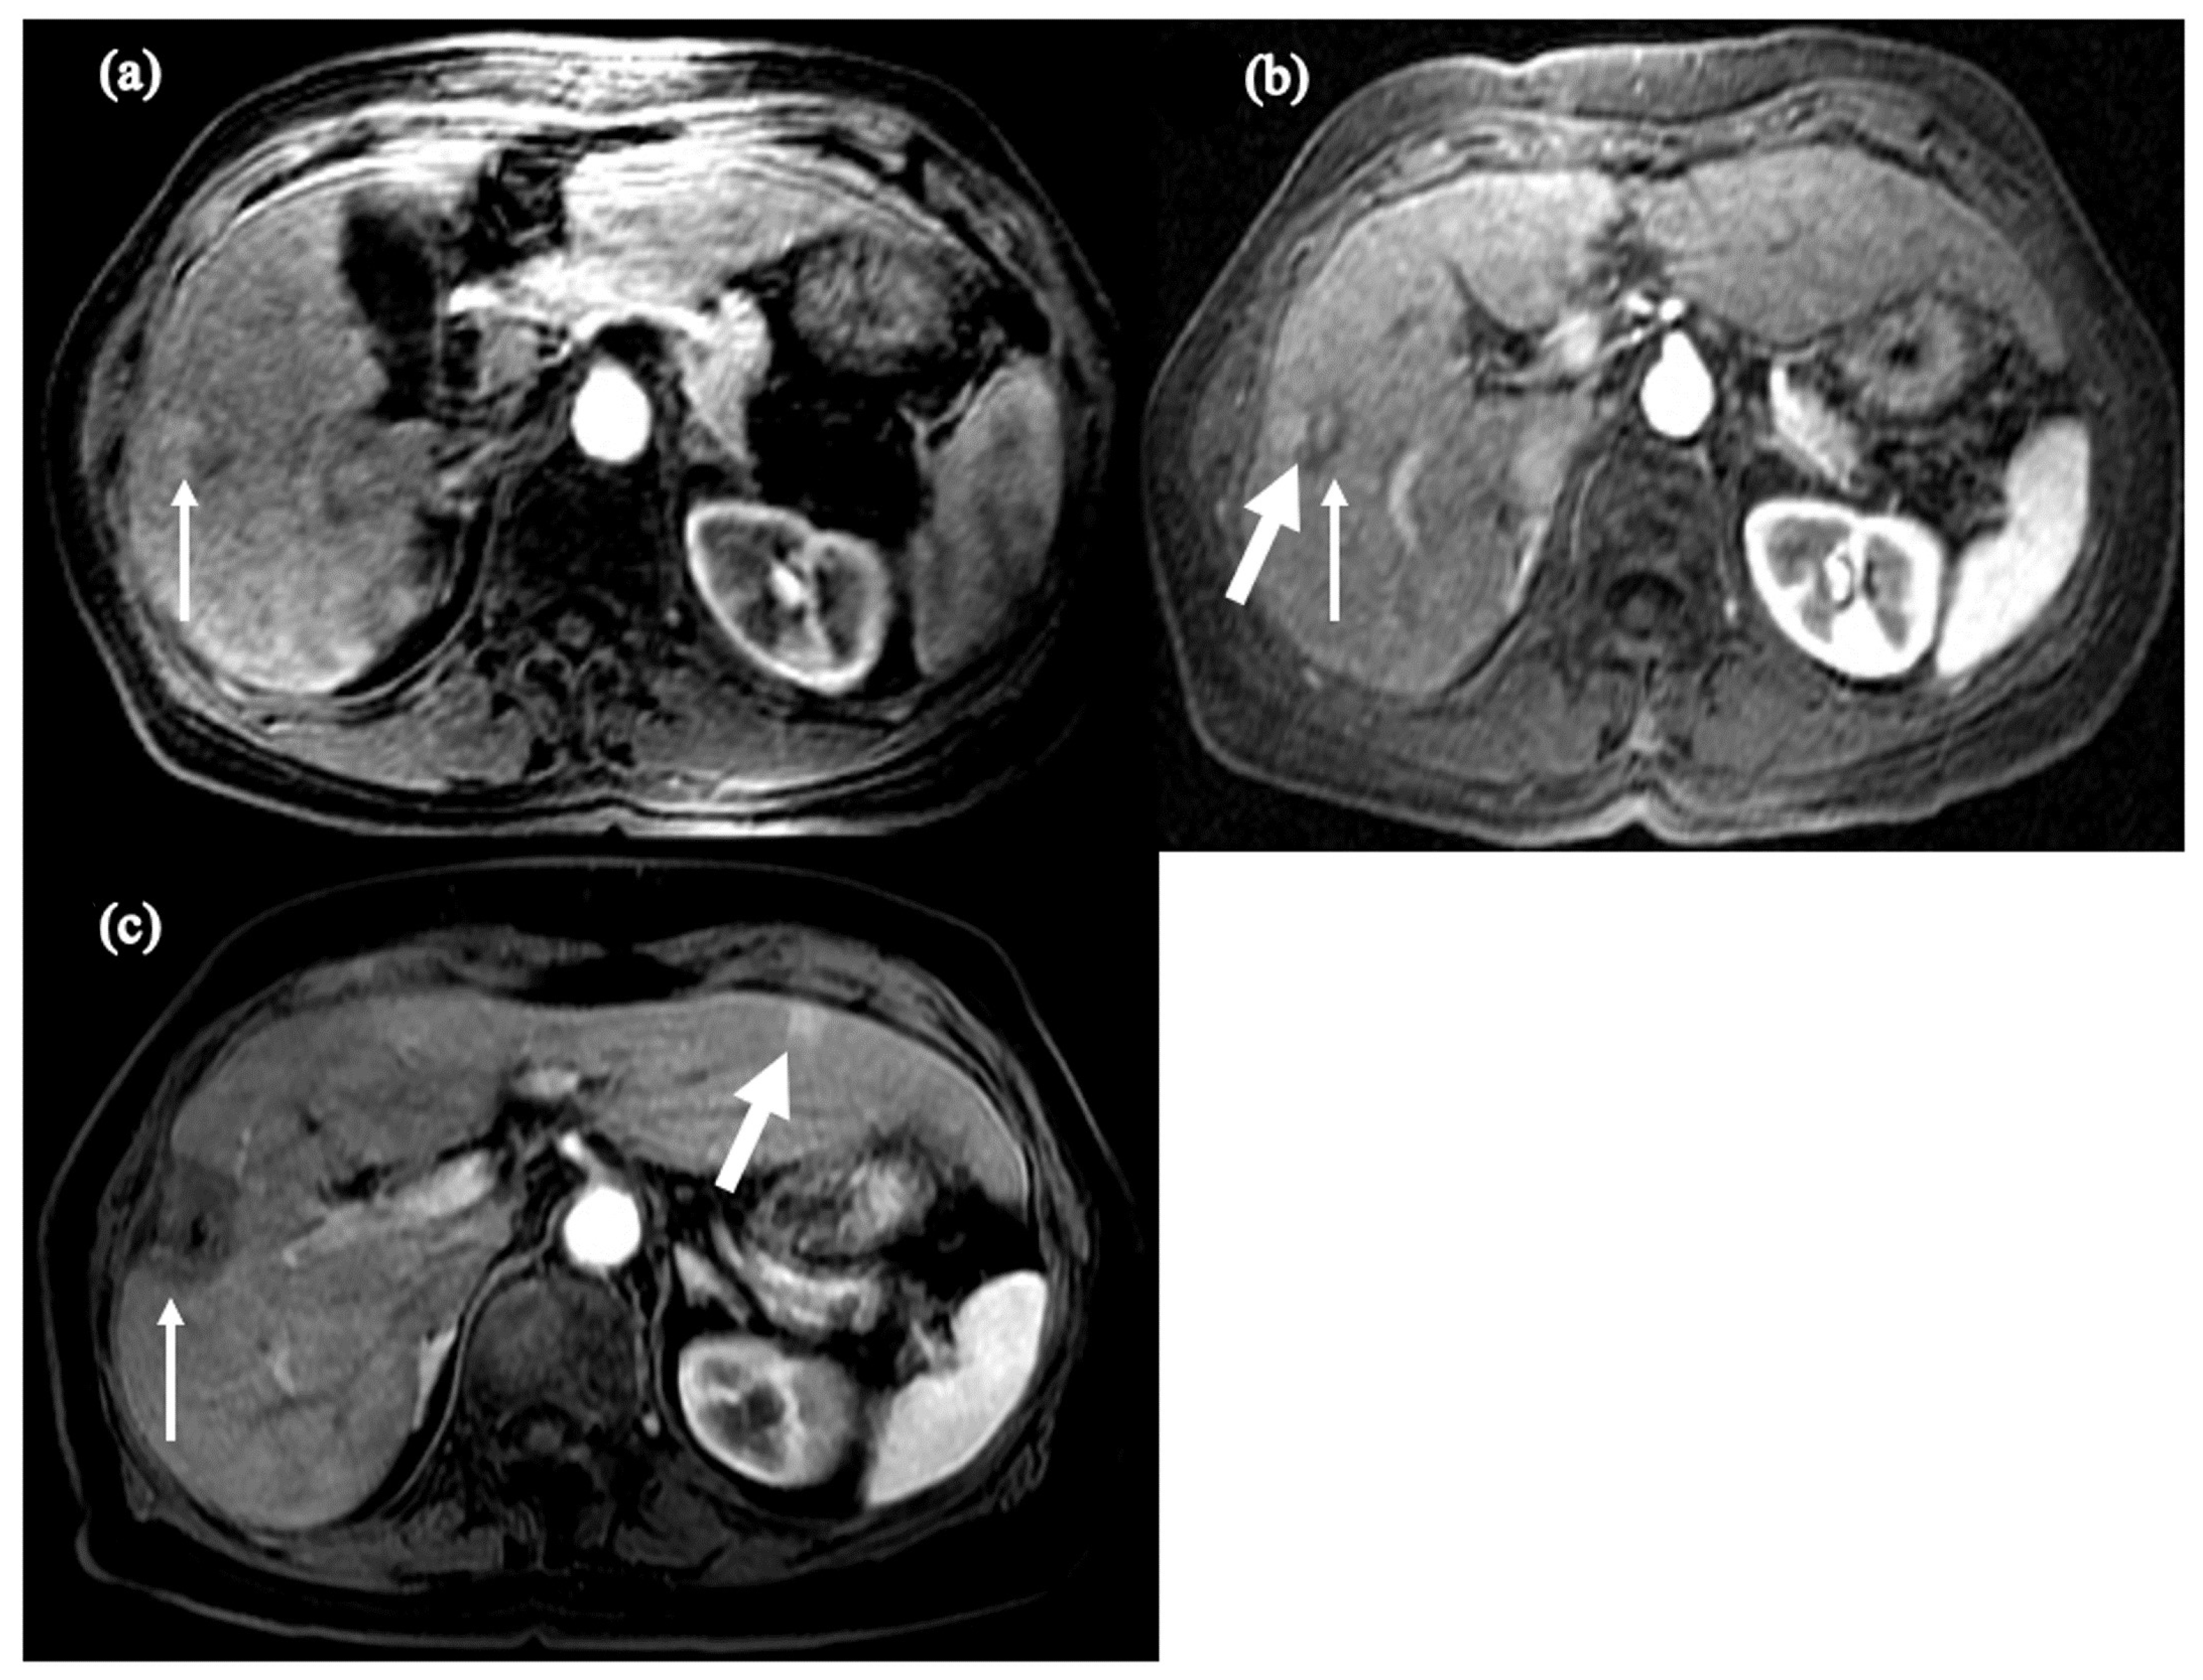

- Shinn, B.J.; Martin, A.; Coben, R.M.; Conn, M.I.; Prieto, J.; Kroop, H.; DiMarino, A.J.; Hann, H.W. Persistent risk for new, subsequent new and recurrent hepatocellular carcinoma despite successful anti-hepatitis B virus therapy and tumor ablation: The need for hepatitis B virus cure. World J. Hepatol. 2019, 11, 65–73. [Google Scholar] [CrossRef] [PubMed]